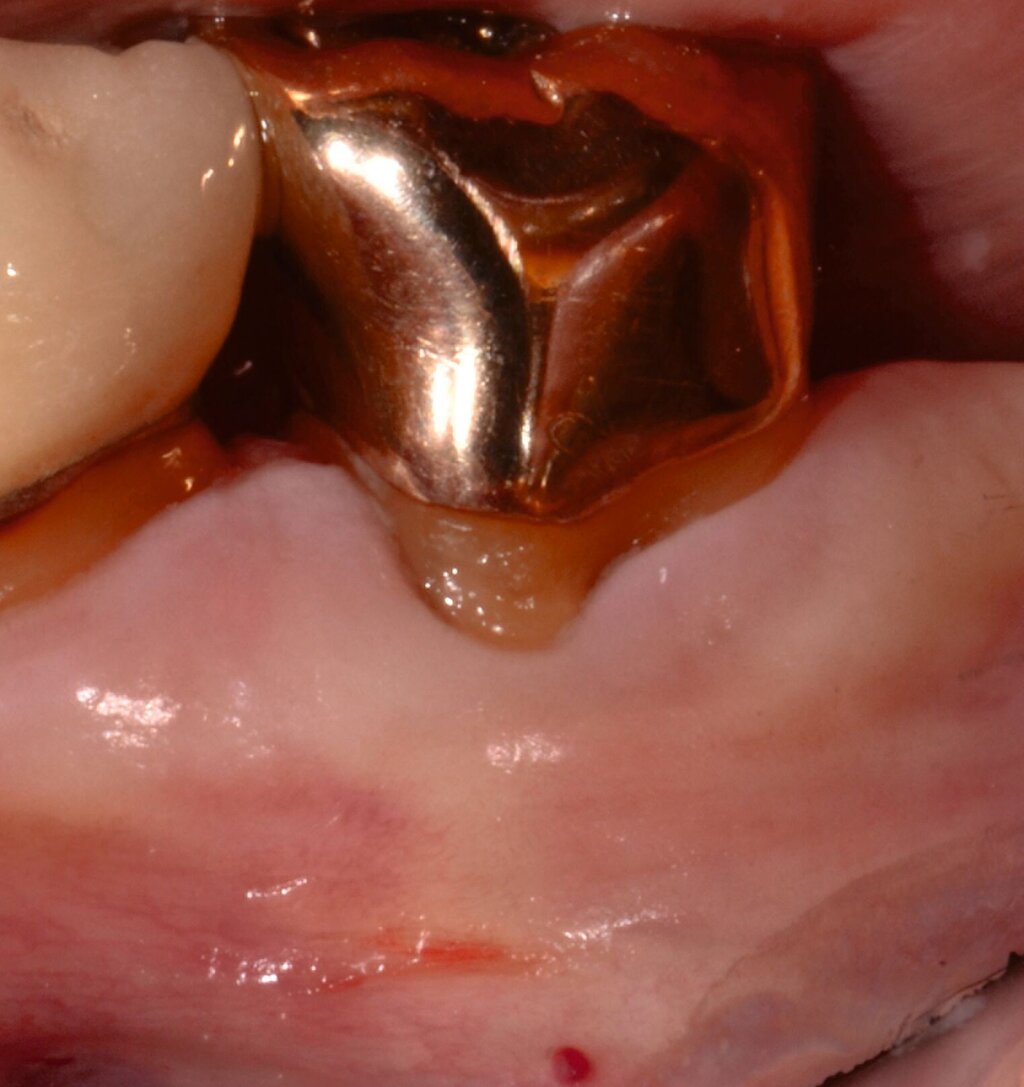

3. Regenerative Parodontalchirurgie

Ziel ist es, einen ausreichenden Zugang zum Defekt für eine sorgfältige Instrumentierung und die Applikation des Biomaterials zu erhalten. Bei isolierten Defekten können vertikale Entlastungsinzisionen verwendet werden. Alternativ kann der Lappen nach lateral zu den benachbarten Zähnen erweitert werden. Keratinisiertes Gewebe sollte durch intrasulkuläre Inzision und die Anhebung eines Mukoperiostlappens erhalten werden. Das Granulationsgewebe wird entfernt und die freiliegenden Wurzeloberflächen werden sorgfältig mit Handinstrumenten, oszillierenden Scalern (optional mit fein diamantierten Spitzen) oder rotierenden Instrumenten gereinigt. Wurzelanomalien wie Schmelzvorsprünge/-perlen sollten entfernt werden. Wenn EMD Teil der Regenerationsstrategie ist, wird es in der Regel nach einer zweiminütigen Wurzelkonditionierung mit Ethylendiamintetraacetat (EDTA) und Spülung mit steriler Kochsalzlösung angewendet. Anschließend kann ein Knochentransplantat/-ersatzmaterial verwendet werden, um den Furkationsdefekt aufzufüllen.

Alternativ kann eine GTR-Barrieremembran mit oder ohne zusätzlichen Defektfüller appliziert werden. Die Barrieremembran wird mit einer resorbierbaren Umschlingungsnaht befestigt, um den Furkationseingang abzudecken und die Wund- und Koagulumstabilisierung zu fördern. Um eine vollständige Abdeckung der Barriere zu ermöglichen, kann das Periost durchtrennt werden, um den Lappen leicht koronal zu verschieben. Der Lappen wird mit einer Umschlingungsnaht und Einzelknopfnähten über den vertikalen Entlastungsinzisionen oder mit interdentalen Nähten im Fall eines lateral extendierten Lappens in einer koronalen Position gesichert. Der Patient wird angewiesen, für einen Zeitraum von bis zu vier Wochen auf die mechanische Plaqueentfernung im Operationsgebiet zu verzichten. Während dieser Zeit werden Chlorhexidin-Spülungen oder -Gel verwendet. Der Patient kehrt zur Kontrolle der Wundheilung nach ein und zwei Wochen zurück, wenn die Nähte entfernt werden. Die Interdentalhygiene und die mechanische Plaqueentfernung werden nach vier Wochen wieder aufgenommen. Zudem wird ein individuelles Recallprogramm zur unterstützenden Parodontitistherapie (UPT) festgelegt.